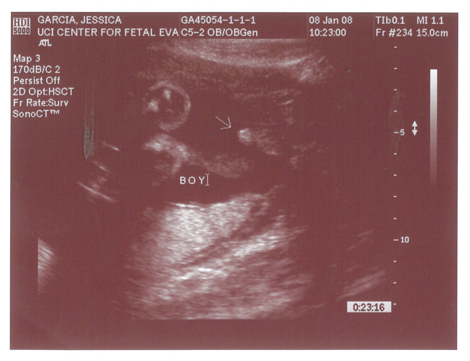

Babies First Pictures!!! ITS A BOY!

Yes we got a new dsmer coming into the world soon. We got our ultrasound today and its gonna be a boy. And shes a lot further along then we had originally thought. Shes due on April 15th which puts her at almost 6.5 months, (and really not showing it.) He weighs currently ~2lbs. He even opened his mouth while on camera which was really cool.

Here are the pics.

Pic 3: NWS Baby Penis! lol

Name:	BabysFirstPics_itsaBoy.jpg

Views:	105

Size:	137.4 KB

ID:	6779